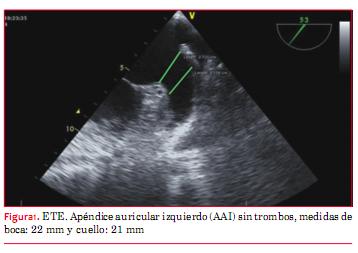

El ecocardiograma transesofágico (ETE) mostró: AAI sin trombos, unilobulado, con diámetro de su boca de 20 mm a 0º y 45º y de 22 mm a 100º. El cuello midió 21 mm de diámetro a 10 mm de la boca sobre el borde interno de la arteria circunfleja a 60º (figura 1).